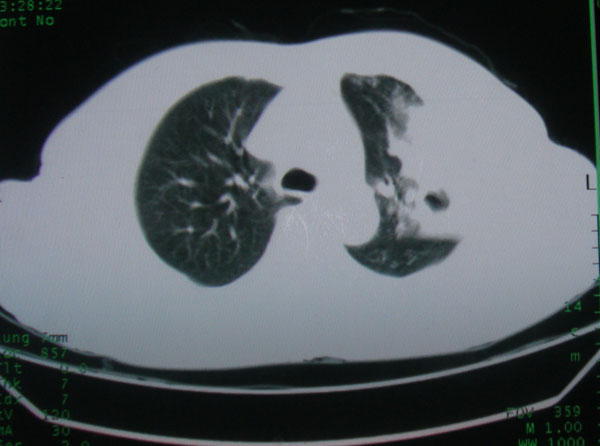

患者男性58岁因二周前起咳嗽,今天胸片示左上肺占位性病变行ct检查,无发热,无咯血痰.

左上肺感染性病变,结核伴空洞形成可能,左上肺膨胀不全

左肺上叶病灶,实变但见含气支气管、空洞但未见壁内结节及积液;

考虑:①感染性病变(包括特殊感染型肺tb)

②肿瘤性病变(考虑患者年龄比较大的关系/所以不排除)

初学者。。。左肺空洞性病变,并可见阻塞性肺不张改变,鉴于患者为老年男性,且临床症状仅有咳嗽,全身中毒症状不明显,所以我首先考虑为左肺癌性空洞并左侧肺门淋巴结转移伴左肺阻塞性肺不张。结核性空洞放于第二位考虑,可以进行相关实验室检查。希望能有病理结果,谢谢!!!!!

左肺上叶实变影,内见支气管充气征及空洞影,病人年龄较大,无发热及结核中毒症状,心影左移,未见纵隔淋巴结肿大;不知实验室检查结果如何?有否嗜酸细胞增多,有没有进行治疗?就目前资料首先考虑1.感染性病变,2.慢性嗜酸性肺炎?可结合实验室检查并短期治疗复查,肺癌不能排除。